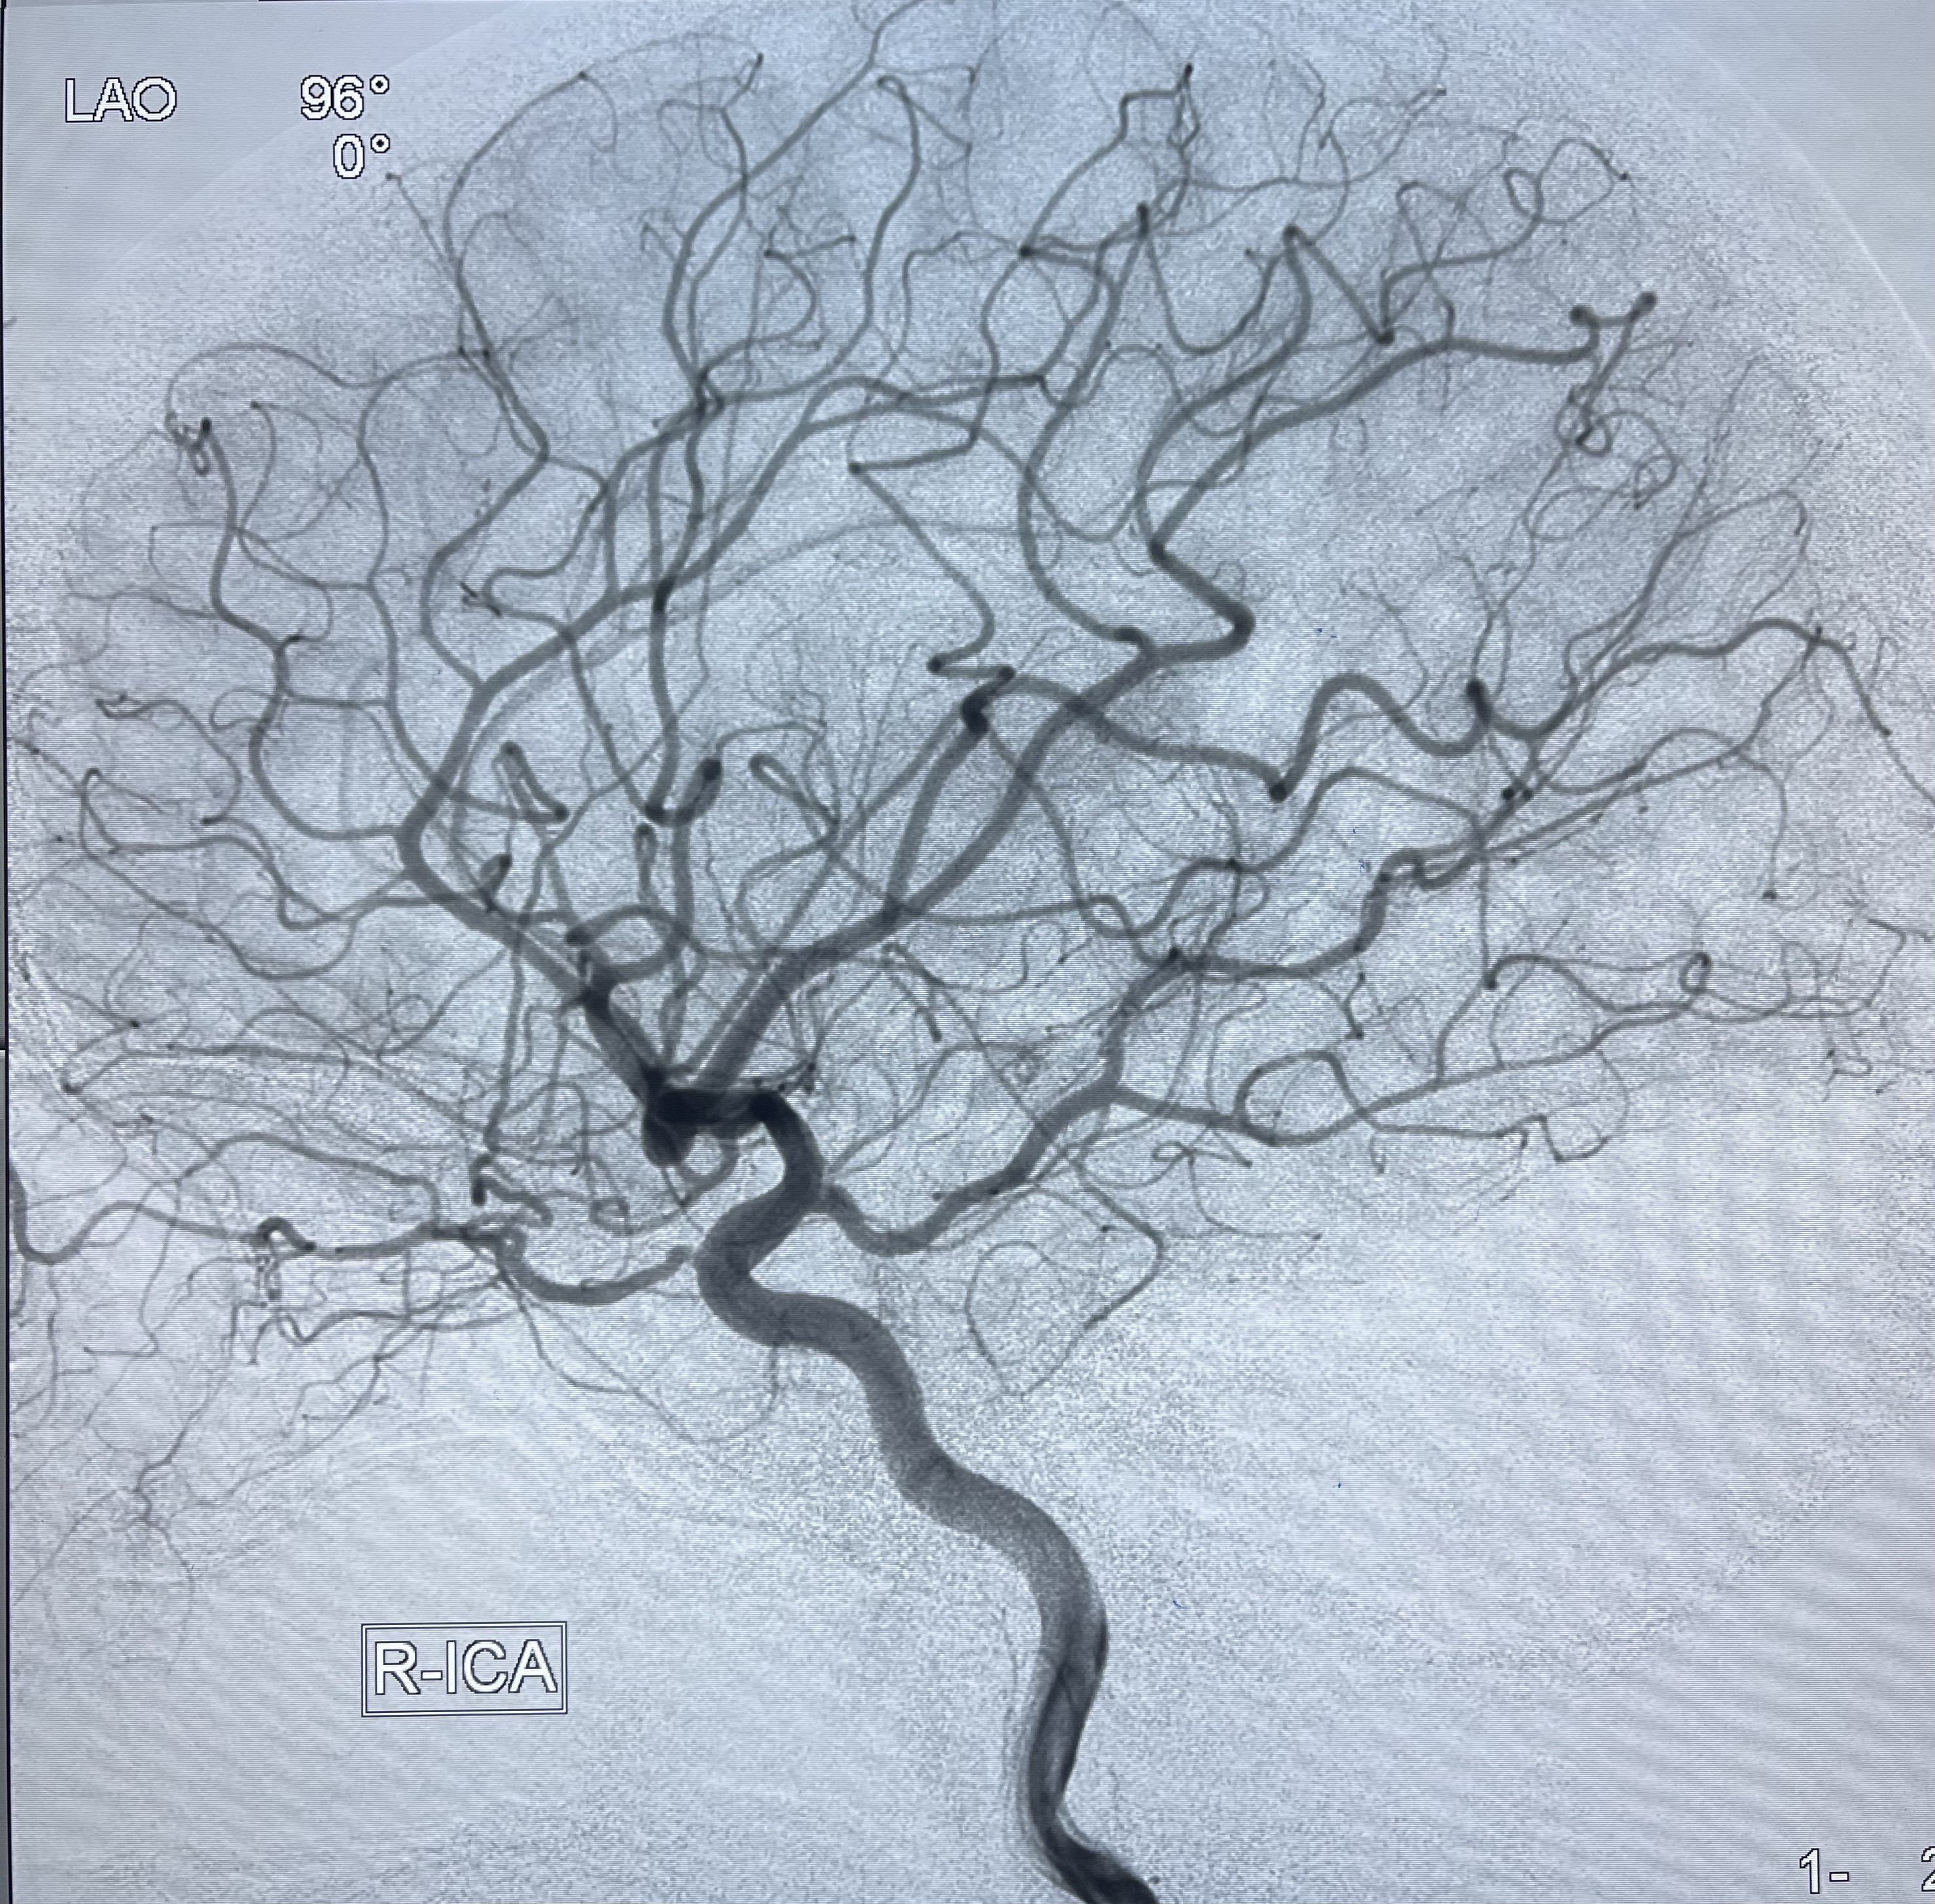

2021-01-07DSA

右侧前交通动脉瘤

箭头所示为左侧A2发出